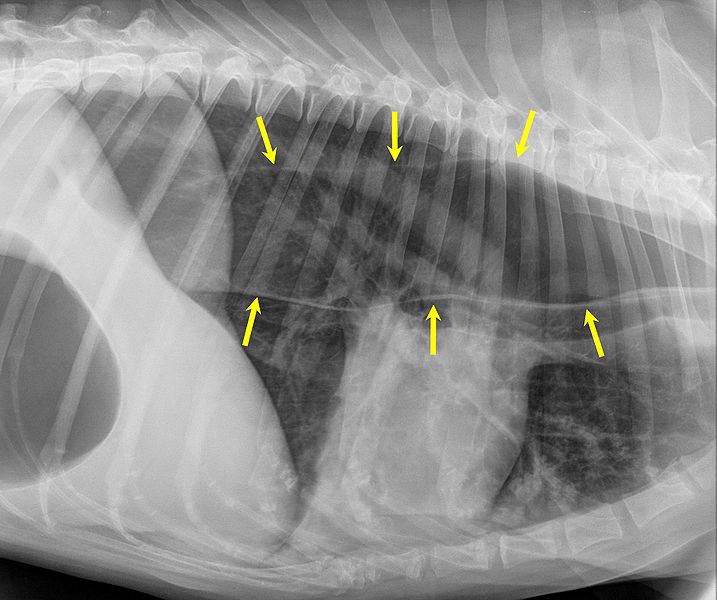

Dackellähme

Als Dackellähme (oder auch Teckellähme) werden die durch einen Bandscheibenvorfall ausgelösten Krankheitssymptome bei Hunden, welche eine genetisch fixierte Knorpelwachstumsstörung (Chondrodystrophie) aufweisen, bezeichnet.

Wie der Name bereits sagt, sind hiervon häufig Dackel betroffen, aber auch Pekinesen, Scottish Terrier, Spaniel, Französische Bulldoggen und Zwergpudel sind für die Erkrankung anfällig.

Die Erkrankung beruht auf einer Degeneration der Bandscheiben.

Diese besteht aus dem peripher liegenden Anulus fibrosus und dem zentral liegenden Bandscheibenkern (Nucleus pulposus). Die vorliegende Chondrodystrophie führt zu einer Umwandlung des elastischen, gallertigen Kernes in knorpelartiges, verkalktes, teilweise abgestorbenes Gewebe, der mit einer zunehmenden Instabilität und Auffaserung des Anulis fibrosus einhergeht (Enchondrosis intervertebralis). Die somit kaum noch elastische und belastbare Bandscheibe kann somit bereits bei kleineren Belastungen oder Traumen reißen: es kommt zum Vorfall des Bandscheibenkerns oder der gesamten Bandscheibe in den Wirbelkanal hinein.

Hierdurch werden Quetschungen und Schädigungen des Nervengewebes verursacht, welche wiederum entsprechende klinische Ausfallserscheinungen der Nervenfunktion nach sich zieht. Die Erkrankung tritt vor allem im jüngeren bis mittleren Lebensalter im Alter zwischen zwei und sieben Jahren auf und betrifft vor allem den mechanisch am stärksten beanspruchten Teil der Wirbelsäule zwischen elftem Brust- und drittem Lendenwirbel, seltener die kaudale Lendenwirbelsäule zwischen fünftem Lendenwirbel und Kreuzbein sowie die Halswirbelsäule zwischen dem zweiten und siebten Halswirbel.

Diagnose

Gemeinsam mit der Rasse des betroffenen Tieres gibt eine neurologische Untersuchung deutliche Anhaltspunkte für die Lokalisation der Schädigung. Dagegen ist das Anfertigen einer einfachen Röntgenaufnahme nicht immer hilfreich, da sich die vorgefallenen Bandscheibenanteile meist im Röntgen nicht deutlich nachweisen lassen. Mittels einer Myelographie ist die Eingrenzung des Schadens jedoch in der Regel möglich.

Letzte Sicherheit über das Ausmaß des Schadens kann eine Magnetresonanztomographie geben.